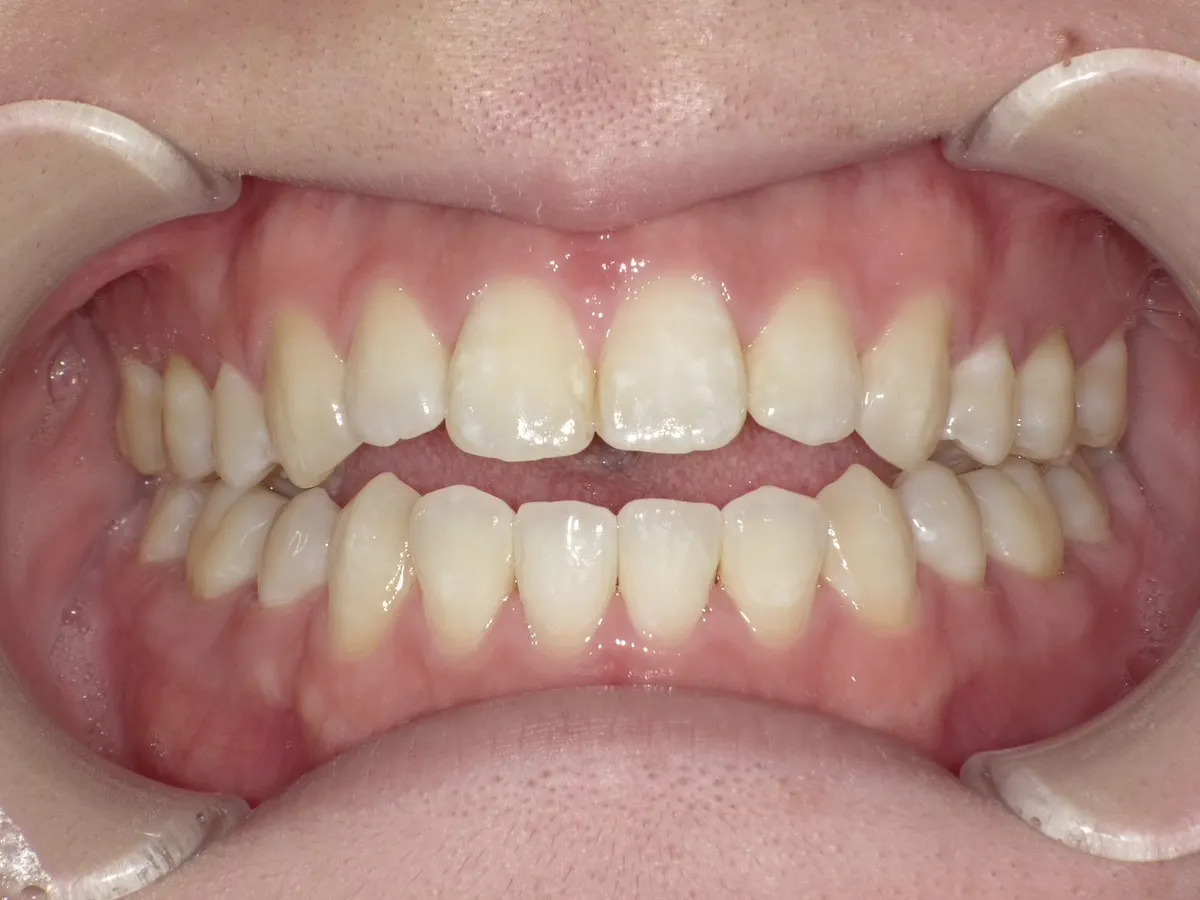

症例1_治療前 症例1_治療後

年齢(年代) 26才(当時)

治療方法 ホワイトブラケット

治療期間 3年

治療総額 825,000円

特記事項 抜歯あり